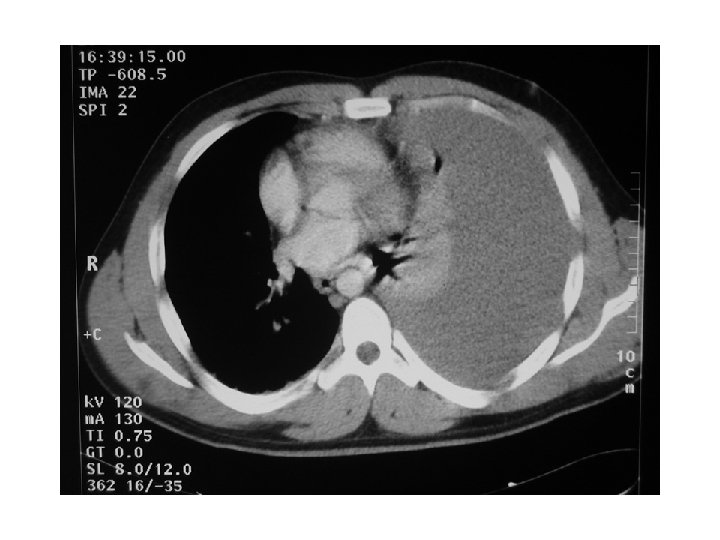

CT scan : infiltration , abcess formation , Lymph node

CXR shows cavity with aspergilloma ( like a ball inside the cavity by CT either able to move or fixed ) called : aspergilloma complex or mycetoma. If it is invasive ( Invasive aspergilloma) , it can lead to infecion , affect the Vessels , Lung Tissue, Bronchi. the pt present with severe hemorrhage. . I think !

§ Investigations ‒ ‒ § Skin test Sputum ( fungal culture) Biopsy (Invasive) ( by CT scan ) CXR Treatment ‒ Medical ( anti fungal ) ‒ Surgical § Indications ‒ A significant aspergilloma ‒ Haemoptysis ‒ Clinical features such as Chronic productive cough , SOB , § Type of resection ‒ Lobectomy ( mainly ) ‒ Pneumonectomy ( Rarely ) ‒ Segmentectomy ( very rarely )